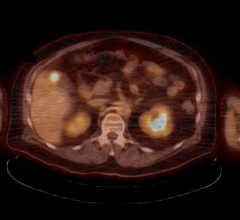

Proton therapy, or proton beam therapy, is a type of radiation therapy used to treat cancer. At a high energy, the positively charged particles can destroy cancer cells.

Proton therapy is becoming more prevalent in cancer treatment as it is the most advanced form of radiation available ...